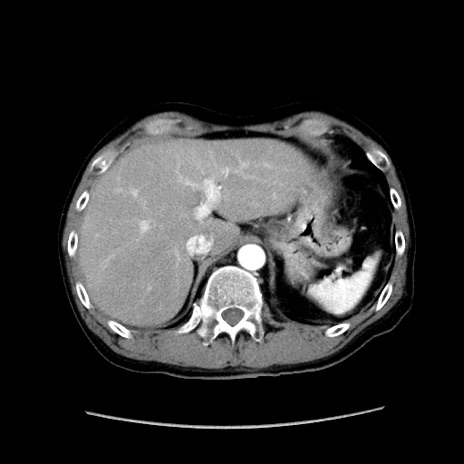

症例37(横断像)

【症例】40歳代 男性

【主訴】腹痛

【現病歴】4時間ほど前に電車に乗車中に臍部上より腹痛出現。徐々に増悪し起立困難となり、救急外来受診。生ものは数日食べていない。今朝お雑煮を食べた。

【身体所見】BT 36.8℃、BP 117/84mmHg、HR 91/min、SpO2 97%、苦悶様、腹部:臍上部広範囲圧痛あり、反跳痛±

【データ】WBC 8100、CRP 0.03